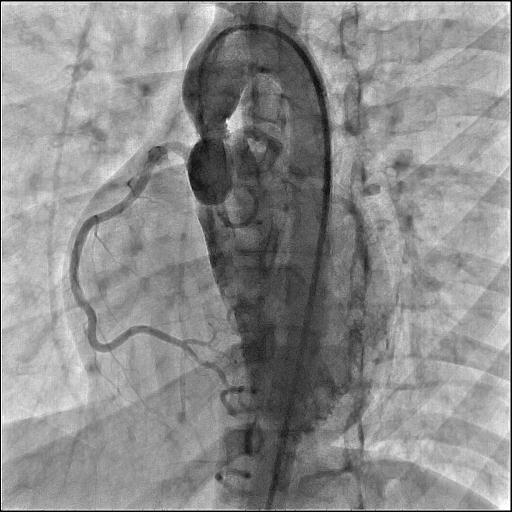

A 2-dimensional transthoracic echocardiogram showed left ventricular hypertrophy with a left ventricle outflow gradient of 88 mm Hg. However, the level of obstruction was not obvious due to a poor transthoracic window secondary to pectus carinatum. Hence, after informed consent, the patient was taken up for cardiac catheterization to look for the anatomical site of obstruction. Cardiac catheterization was performed via right femoral artery acces, and a 6-French pigtail crossed the aortic valve without any resistance. Aortogram revealed narrowing at the sinotubular junction (STJ), which was suggestive of SVAS, and explained the failure of the previously attempted AVBD (Figure, Video). The coronary arteries showed a normal origin and there was no arch vessel stenosis. Catheter pullback from the left ventricle to the aorta showed a peak-to-peak gradient of 74 mm Hg. The patient underwent SVAS repair, which was performed by non-coronary cusp and right coronary cusp augmentation with aortoplasty using an autologous glutaraldehyde-fixed pericardial patch.